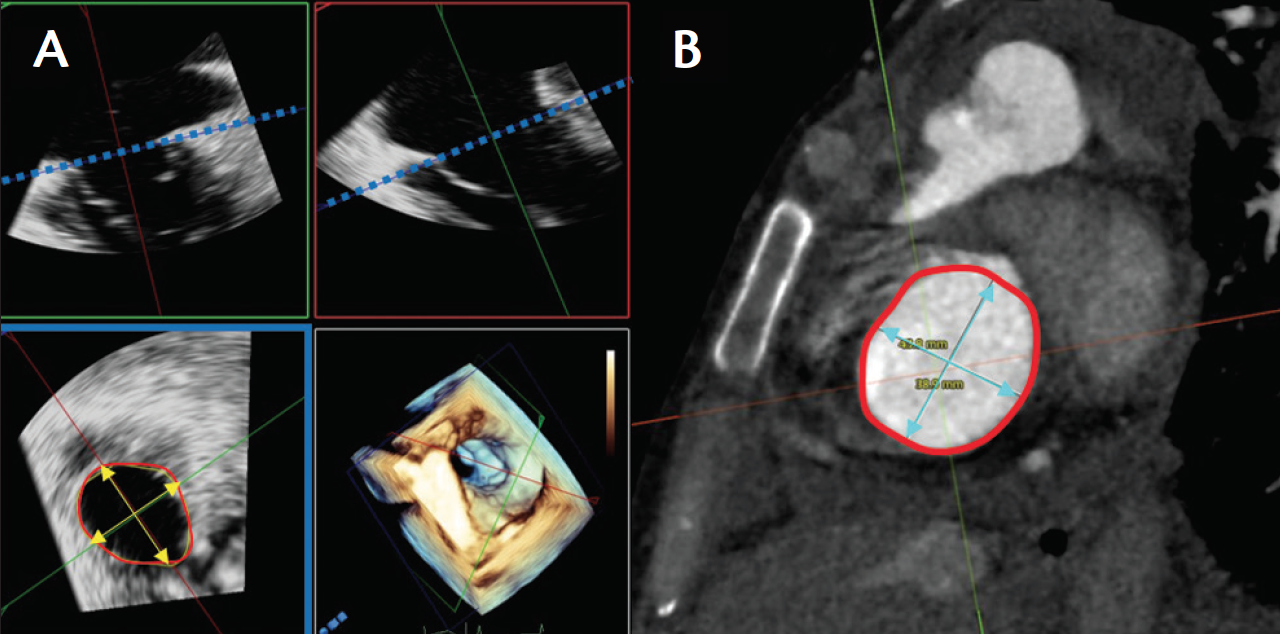

Figure 1. Three-dimensional TEE and CT measurements of the tricuspid annulus. Multiplanar reconstruction of the tricuspid annulus on 3D TEE taken from the deep esophageal view (A). The blue-framed panel shows the annular area and dimension measurements of the tricuspid annulus. Plane of the tricuspid annulus on CT with similar measurements (B).

Given the complex, 3D anatomy of both the tricuspid annulus and right ventricle, it is likely that 3D imaging modalities such as 3D echocardiography, CT scanning (Figure 1), and cardiovascular MRI will replace current measurements, which primarily rely on 2D imaging.69-71 There are some challenges to imaging the right heart. Homogeneous enhancement of the structures around the tricuspid valve annulus may be difficult, with streak artifact arising from high-attenuation superior vena cava contrast enhancement mixing with unenhanced blood of the inferior vena cava. These artifacts may be reduced by a femoral vein injection of contrast or, ideally, simultaneous injections.69,72 Assessing the end-systolic tenting distance and tricuspid annular dimensions, as well as right ventricular volumes and function, is feasible by CT in patients with functional TR.70,73

Kabasawa et al73 showed that preoperative leaflet tenting angles correlated with TR severity, and a tenting distance of > 7.2 mm predicted recurrent TR ≥ 2+ after surgical annuloplasty. Furthermore, van Rosendael et al70 showed that patients with TR < 3+ have significantly smaller CT annular measurements (anteroposterior diameter; septal-lateral diameter, perimeter, and area) and lower ventricular volumes. Patients with TR ≥ 3+ had significantly larger tenting angles of the septal and anterior leaflets but not of the posterior leaflet. Significant predictors of TR included pulmonary artery systolic pressure, RV end-systolic volume, and anteroposterior tricuspid annular diameter.

Other studies have shown that CT-defined annulus area correlated strongly with right and left atrial volume, and the annulus shape changed from elliptical to circular in moderate/severe TR.32 Atrial enlargement occurs before right ventricular dilation, which occurs late, when TR is severe. Atrial volume and tricuspid annular dilation may be early and sensitive indicators of significant TR.